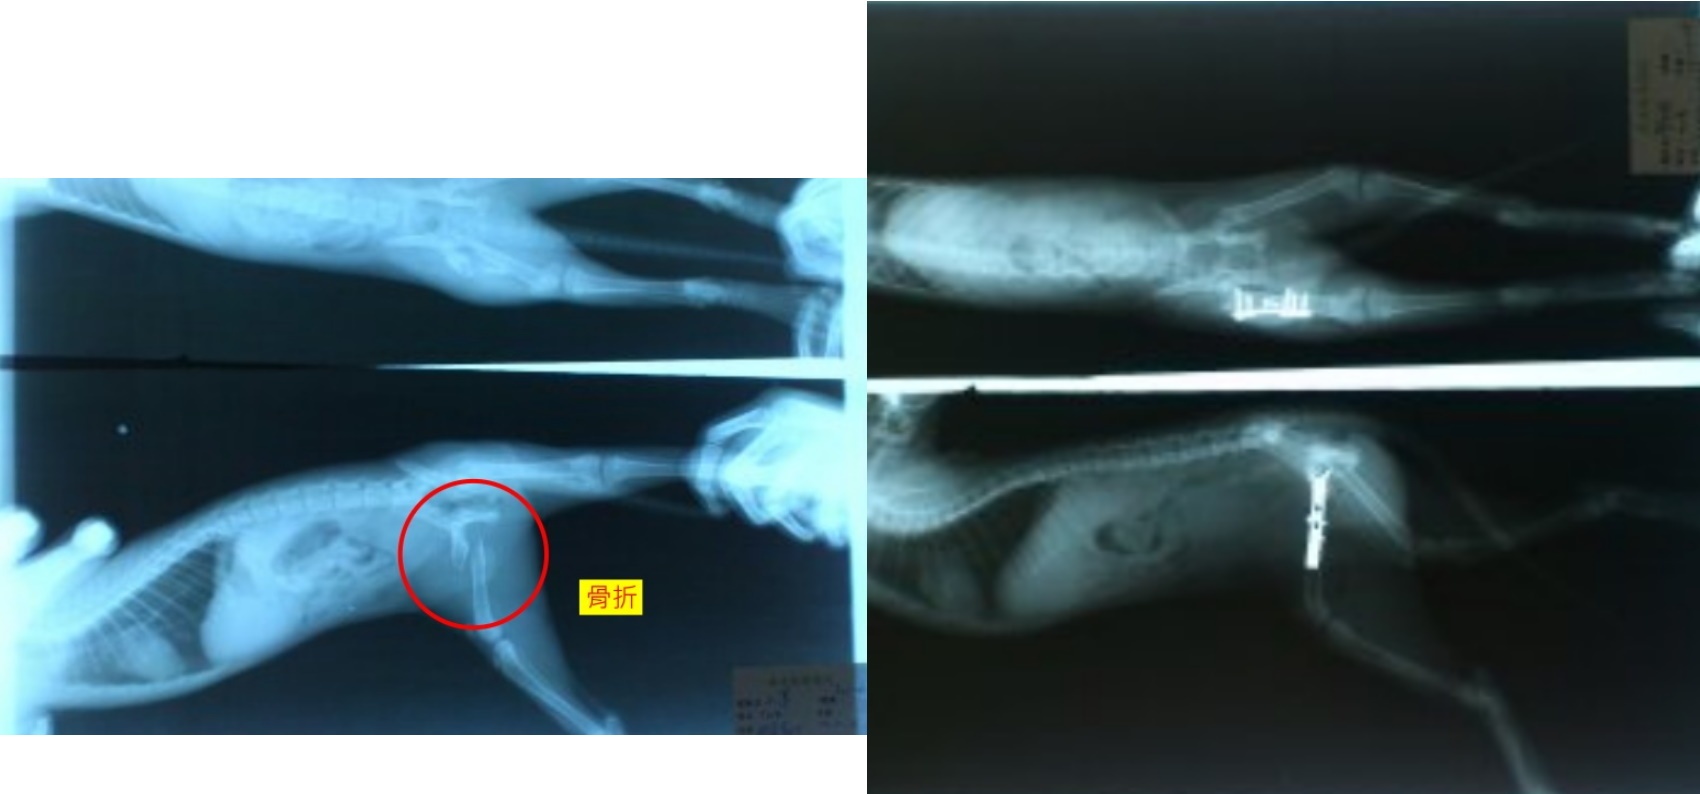

主題: 被狗咬得可憐小貓 申請者姓名: 林煜翔 花色: 申請日期: 2013-11-14 15:59:12 申請者部落格: 申請者臉書網址: ff00111703@yahoo.com.tw 所在縣市/合作醫院: 桃園縣/綠光動物醫院 治療費用: 16000元 需求人數: 18人 已結案 (2014-01-10 17:51:24) 報名人員: Faafaa(已付款)、神小貓(已付款)、Janice Wu(已付款)、00(已付款)、Tracy Ho、Eli Hsiao、Sylvia Chang、Eli Hsiao、yymeow(已付款)、Annie Hsu(已付款)、lin789 x2(已付款)、davidlai(已付款)、江萬田、江萬田(已付款)、蔡秀芳(已付款)、tau511(已付款)、Han Chang、曹淯瑋(已付款)、ERic YU(已付款)、戀糖bear(已付款)、曹小文(已付款)、沈明明(已付款)、Jessica、曹小文(已付款)、 候補人員: 賣摳賣摳、 動物病情說明: 開南大學疑似被狗咬傷的流浪小橘貓,緊急捕捉送醫X光撿查發現右大腿骨折、虛弱,上點滴、保溫等狀況穩定,要趕快進行手術,因為小貓癒合速度數很快,怕骨頭亂長影響行走,等食慾恢復,狀況穩定一些,立刻就進行手術,小貓很爭氣耐過手術,復原良好,但外意發現,小貓的肚子有被咬了一個破洞,醫師觸診洞約一公分左右,有脂肪從洞中掉入皮下,但尚無大礙。由於才剛做完骨折手術,醫師建議狀況再穩定一點之後再進行疝氣手術,小貓在醫師們細心照顧下,慢慢康復情況穩定,已經進行第二次手術縫補疝氣。

咪很親人,人見人愛,有許多貓友看了都非常想認養牠。預計11/19日可以拆除腹部的縫線,出院,目前暫定由本人林煜翔會先帶回家照顧,並帶回醫院做後續門診追蹤。